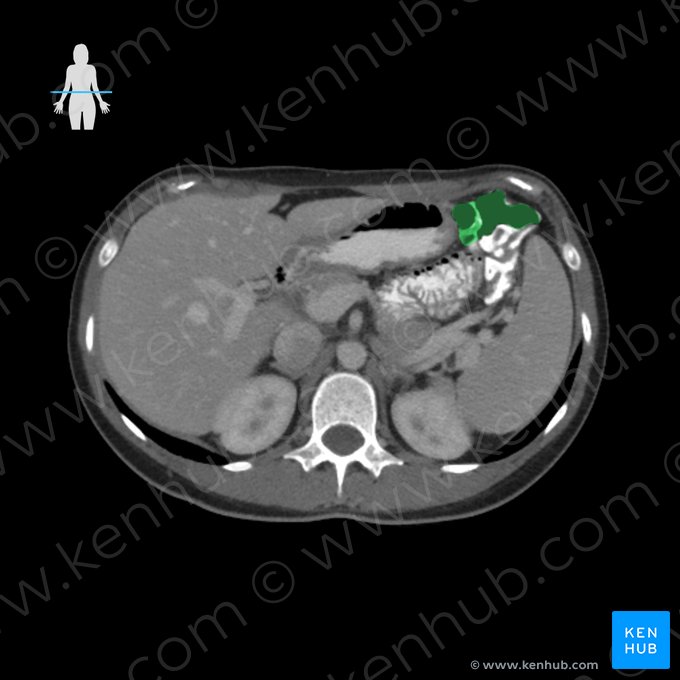

Cólon sigmoide

O cólon sigmoide possui o formato da letra “S”, e cursa desde a fossa ilíaca esquerda até a terceira vértebra sacra (junção retosigmoide). Esta parte do cólon é intraperitoneal. Ela conecta-se à parede pélvica pelo mesocólon sigmoide.

A doença de Crohn é uma doença inflamatória intestinal crônica de origem desconhecida, que pode afetar qualquer parte do trato alimentar, mas mais frequentemente afeta o íleo terminal e o cólon. Normalmente existem múltiplos focos inflamatórios, levando a formação de múltiplas úlceras na parede intestinal. Os sintomas mais comuns são febre, dor abdominal, diarreia e perda de peso. A doença de Crohn normalmente é diagnosticada por exames endoscópicos e radiológicos do abdômen, e geralmente é tratada com imunossupressores.